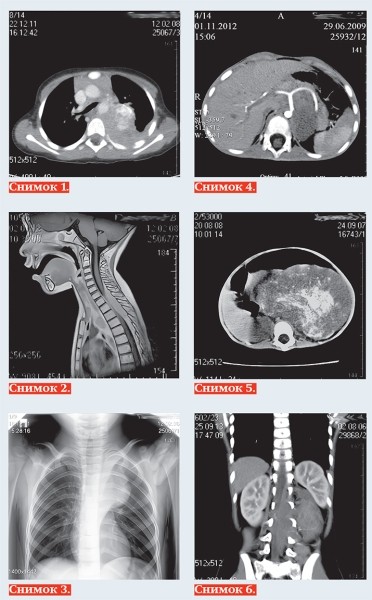

Тканевыми характеристиками нейробластомы являются: мягкотканная масса +25+35 HU на КТ (снимок 1), с гипоинтенсивным МР-сигналом на Т1-ВИ, изо/слабогиперинтенсивным сигналом на Т2, Т2 dark fluid — ВИ (снимок 2), негомогенная за счет кровоизлияний, очаговой кальцинации и некротических изменений, с умеренным контрастированием в паренхиматозную фазу, умеренной рестрикцией диффузии на МРТ.

Чаще всего нейробластома локализуется паравертебрально в реберно-позвоночной борозде по ходу симпатических ганглиев: в забрюшинном пространстве, надпочечниках, заднем средостении (снимок 3), полости таза, в области шеи. Генерализация опухоли с метастазированием в кости выявляется в 20 % случаев, в печень — 10 %, реже в легкие, головной мозг, подкожную клетчатку, при этом характерно поражение периорбитальных мягких тканей (1–5 %).

К наиболее важным визуально определяемым признакам опухоли (IDRF) относятся: поражение двух и более частей тела, вовлечение в опухоль более 50 % периметра артериального сосуда

(снимок 4), сдавление вены без визуализации ее просвета, инфильтрация прилежащего органа (снимок 5), компрессия трахеи и главных бронхов, инвазия сосудистых ножек почек, распространение в спинно-мозговой канал более трети просвета (снимок 6).